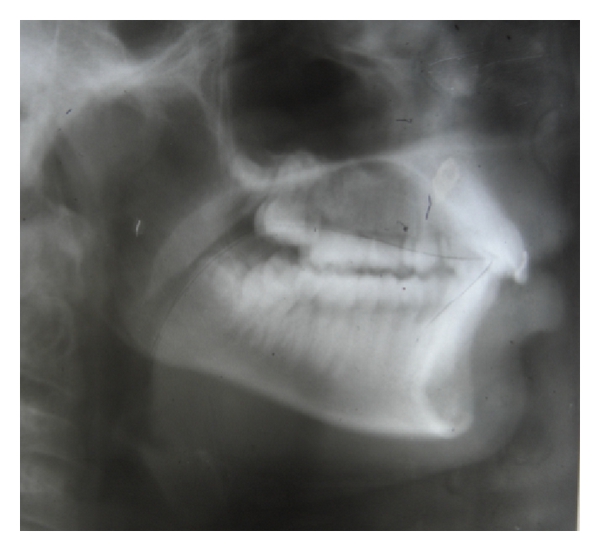

A 13-year-old female patient presented to the Department of Orthodontics and Dentofacial Orthopaedics, Sri Hasanamba Dental College, Hassan, India, with a complaint of forwardly placed upper and lower front teeth. The extraoral examination of the patient showed good facial symmetry, convex profile, acute nasolabial angle, incompetent lips and shallow mentolabial sulcus. Intraoral examination showed class I molar and canine relation on either sides, rotated second premolars in all quadrants, proclined upper and lower anteriors and increased overjet and overbite with anterior traumatic bite. Functional examination suggested that she had tongue thrusting habit which was confirmed by palatography (Figure 3) (palatography involves recording the contact surface of the tongue with the palate and teeth while the patient produces speech sounds such as S or while swallowing). A thin uniform layer of contrasting, precise impression material was applied to the patient’s tongue with a spatula. Once the tongue movement (swallowing) was carried out, the palatogram was documented photographically using a surface mirror. The abnormal position of the tongue was also confirmed by tracing the pretreatment lateral cephalogram (Figure 4). The case was diagnosed as bimaxillary dentoalveolar protrusion with simple tongue thrusting habit. It was decided to eliminate the etiology of the malocclusion at the first phase and then proceed to the fixed appliance phase.

The patient was recalled for checkup every month and after 6 months the appliance was removed and checked for the tongue position and swallowing pattern. Functional examination showed that the patient had changed her swallowing from an infantile to mature pattern, which was confirmed by palatography (Figure 5). A lateral cephalogram was taken to confirm the tongue position at rest which showed a more superior and normal tongue posture. The dorsal part of the tongue was resting on the palate and the tip was place behind the upper incisor in the area of the incisive papilla (Figure 6). The HHCA was cemented back to retain the achieved correction and the second phase of correction using fixed appliance was started. This hybrid appliance proved to be highly effective in correcting the tongue thrusting habit in a short span of six months.